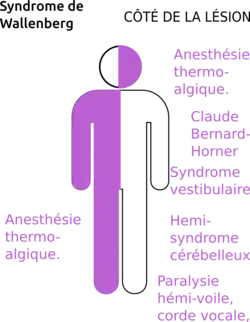

Le tableau clinique complet comporte à la fois des signes neurologiques du côté de la lésion, mais aussi du côté opposé[3].

Opposés à la lésion

On note du côté contro-latéral à la lésion une anesthésie à la chaleur et de la douleur de tout l'hémicorps, plus marquées au niveau des membres et épargnant la face[3]. Cette expression clinique est due à la lésion du faisceau spinothalamique[3].

Du côté de la lésion

Du côté de la lésion on pourra noter une anesthésie à la chaleur ainsi qu'à la douleur au niveau de la face (par atteinte du trijumeau)[3]. On pourra aussi relever[3] :

- un syndrome de Claude-Bernard-Horner ;

- une paralysie de :

- l'hémi-voile,

- l'hémi-pharynx,

- de la corde vocale,

- un syndrome vestibulaire ;

- un hémi-syndrome cérébelleux.